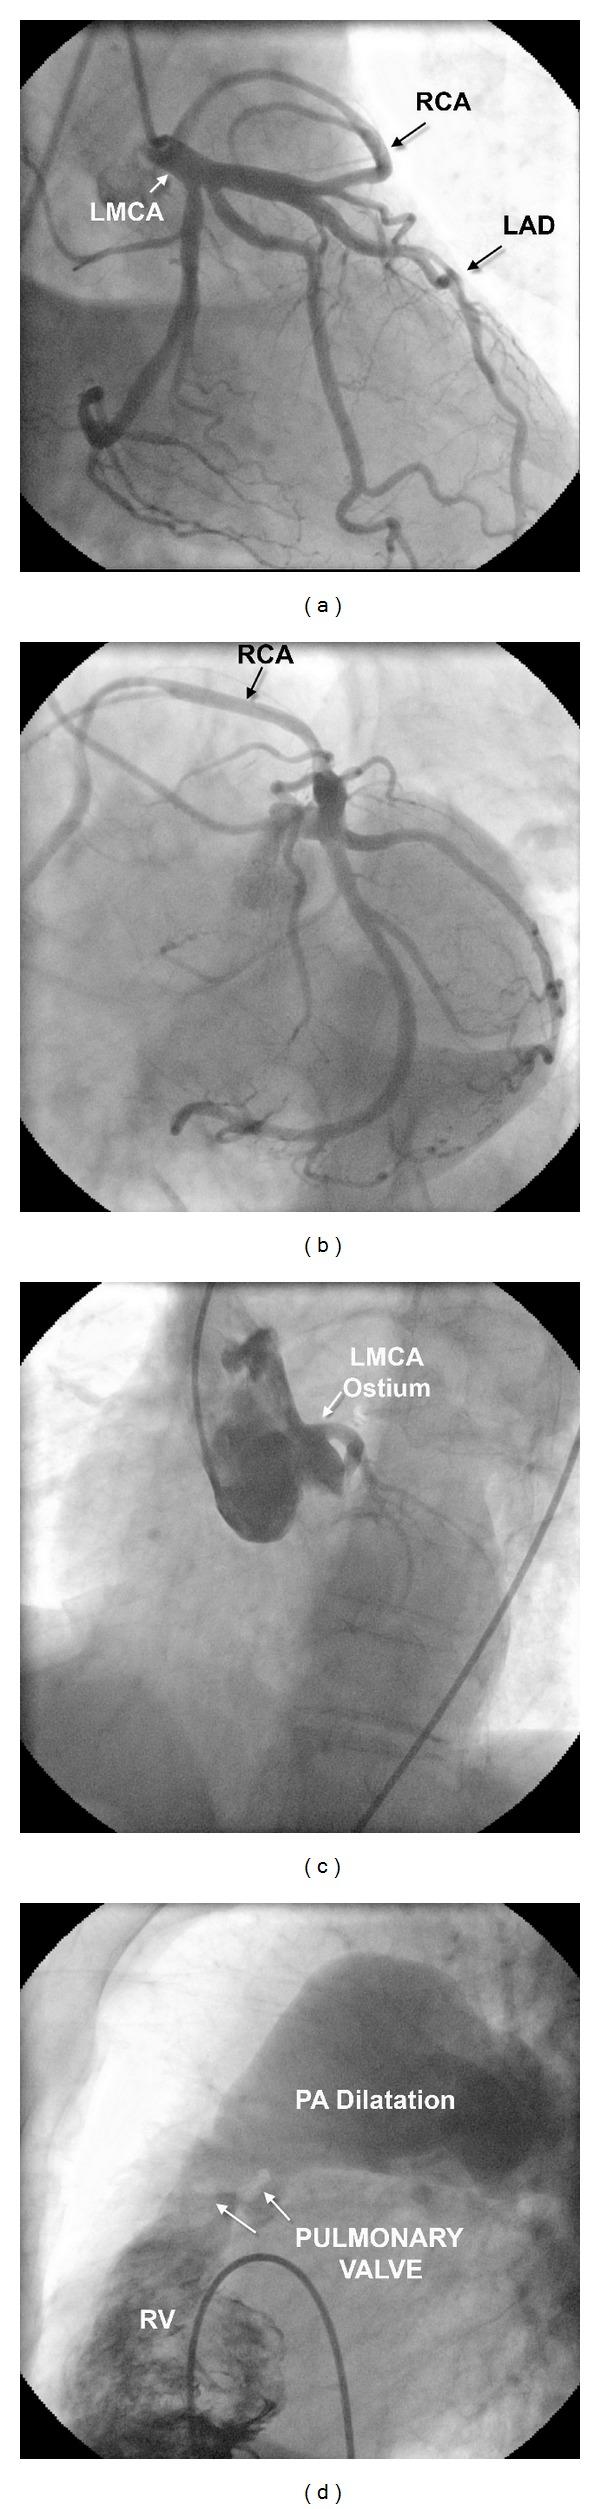

一名先天性肺动脉瓣狭窄患者的右冠状动脉起源于左前降支动脉。

Right coronary artery originated from the left anterior descending artery in a patient with congenital pulmonary valvular stenosis.

The single coronary artery, anomalous origin of the right coronary artery from the left anterior descending artery, is a benign and very rare coronary artery anomaly. We firstly present a case with this type of single coronary artery and congenital pulmonary valvular stenosis with large poststenotic dilatation.

单冠状动脉,即右冠状动脉起源于左前降支,是一种良性且非常罕见的冠状动脉异常。我们首次报道了一例患有此类单冠状动脉并伴有先天性肺动脉瓣狭窄及严重狭窄后扩张的病例。